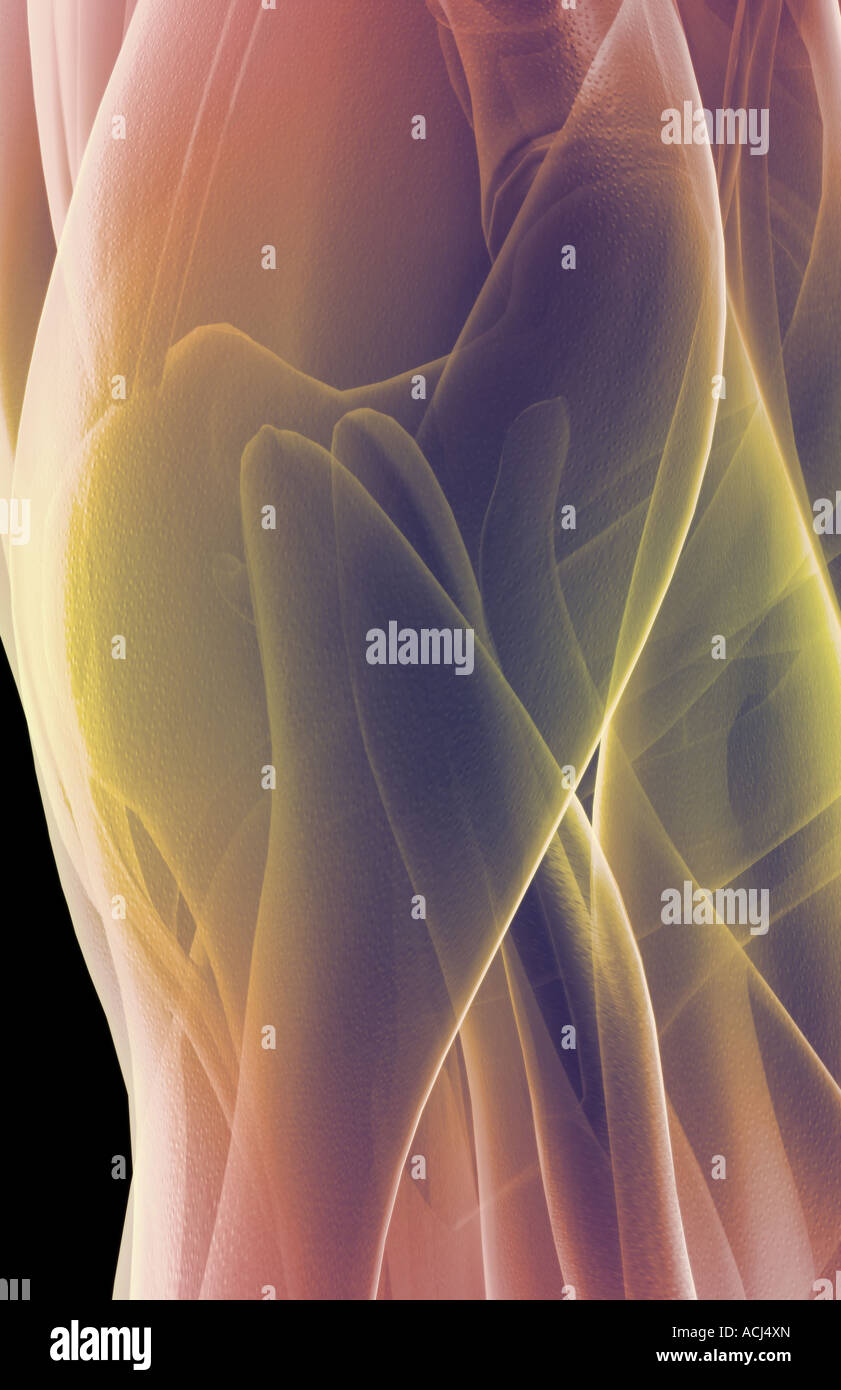

The muscles of the hip Stock Photohttps://www.alamy.com/image-license-details/?v=1https://www.alamy.com/stock-photo-the-muscles-of-the-hip-13166588.html

The muscles of the hip Stock Photohttps://www.alamy.com/image-license-details/?v=1https://www.alamy.com/stock-photo-the-muscles-of-the-hip-13166588.htmlRFACJ4XN–The muscles of the hip

The muscles of the hip Stock Photohttps://www.alamy.com/image-license-details/?v=1https://www.alamy.com/stock-photo-the-muscles-of-the-hip-13212764.html

The muscles of the hip Stock Photohttps://www.alamy.com/image-license-details/?v=1https://www.alamy.com/stock-photo-the-muscles-of-the-hip-13212764.htmlRFACR2AN–The muscles of the hip